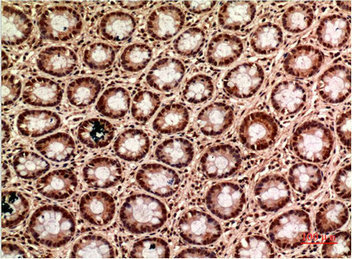

Immunohistochemical analysis of paraffin-embedded Human Colon Carcinoma Tissue using TUBG1 Monoclonal Antibody diluted at 1:200.